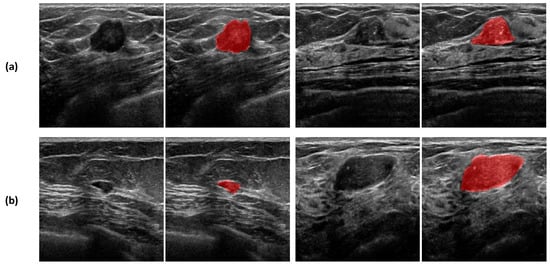

4. Convolutional Neural Network for Breast Cancer Diagnosis

4.1. Datasets